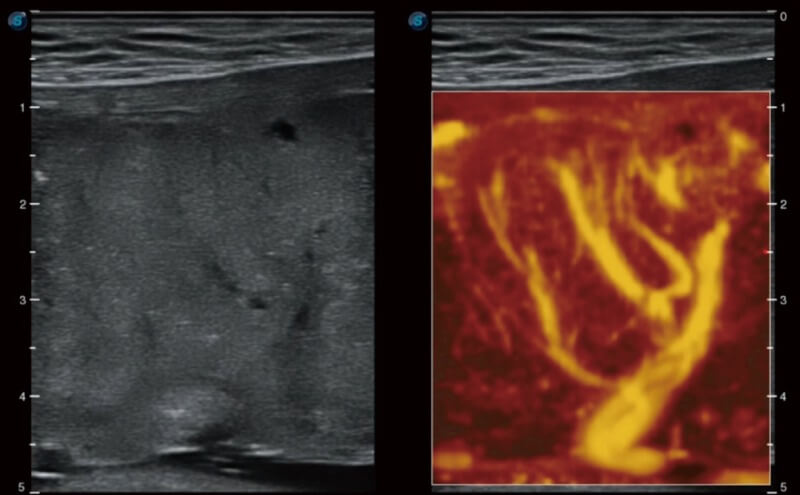

Mit Auto IMT wird die Messung der Dicke der vorderen und hinteren Intima-Media viel einfacher durch einfaches Platzieren des ROI.